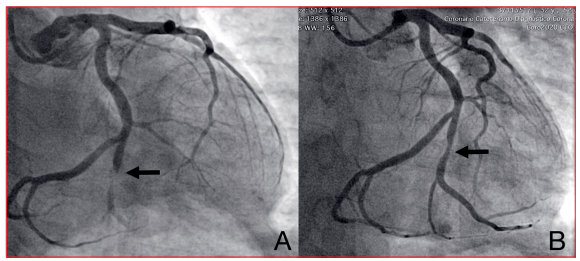

Paciente de sexo masculino, 52 años, tabaquista. Se presentó en emergencia donde se realizó diagnóstico de IAM inferoposterior Killip y Kimball I de dos horas de evolución. Se le realizó cineangiocoronariografía (CACG) de emergencia que evidenció oclusión trombótica de ramo marginal obtuso con flujo distal TIMI 1 (figura 1A). Se realizó aspiración manual del trombo y se dilató la lesión con balón. En la angiografía de control se evidenció flujo TIMI 3 y estenosis residual moderada (figura 1B). Concomitantemente se constató cese del dolor y renivelación del segmento ST. Se realizó OCT intracoronaria, en la cual se observó un extenso trombo rojo a nivel del sitio previamente ocluido (figura 2). Se inició tratamiento farmacológico con base en ácido acetilsalicílico (AAS), clopidogrel, heparina de bajo peso molecular e inhibidores de la glicoproteína IIb-IIIa. Con respecto al implante de stent, frente a la acalmia del dolor, la renivelación del segmento ST y la evidencia de trombo como principal responsable de la obstrucción, con una estenosis residual moderada, se decidió diferirlo, y esta conducta quedó supeditada a la evolución y a resultados de nuevos estudios de imagen.

Figura 1 A) Coronariografía en proyección caudal donde se observa oclusión aguda del primer ramo marginal obtuso con imagen de trombo endoluminal (flecha). B) Imagen final luego de realizar aspiración manual del trombo y dilatación con balón (flecha).